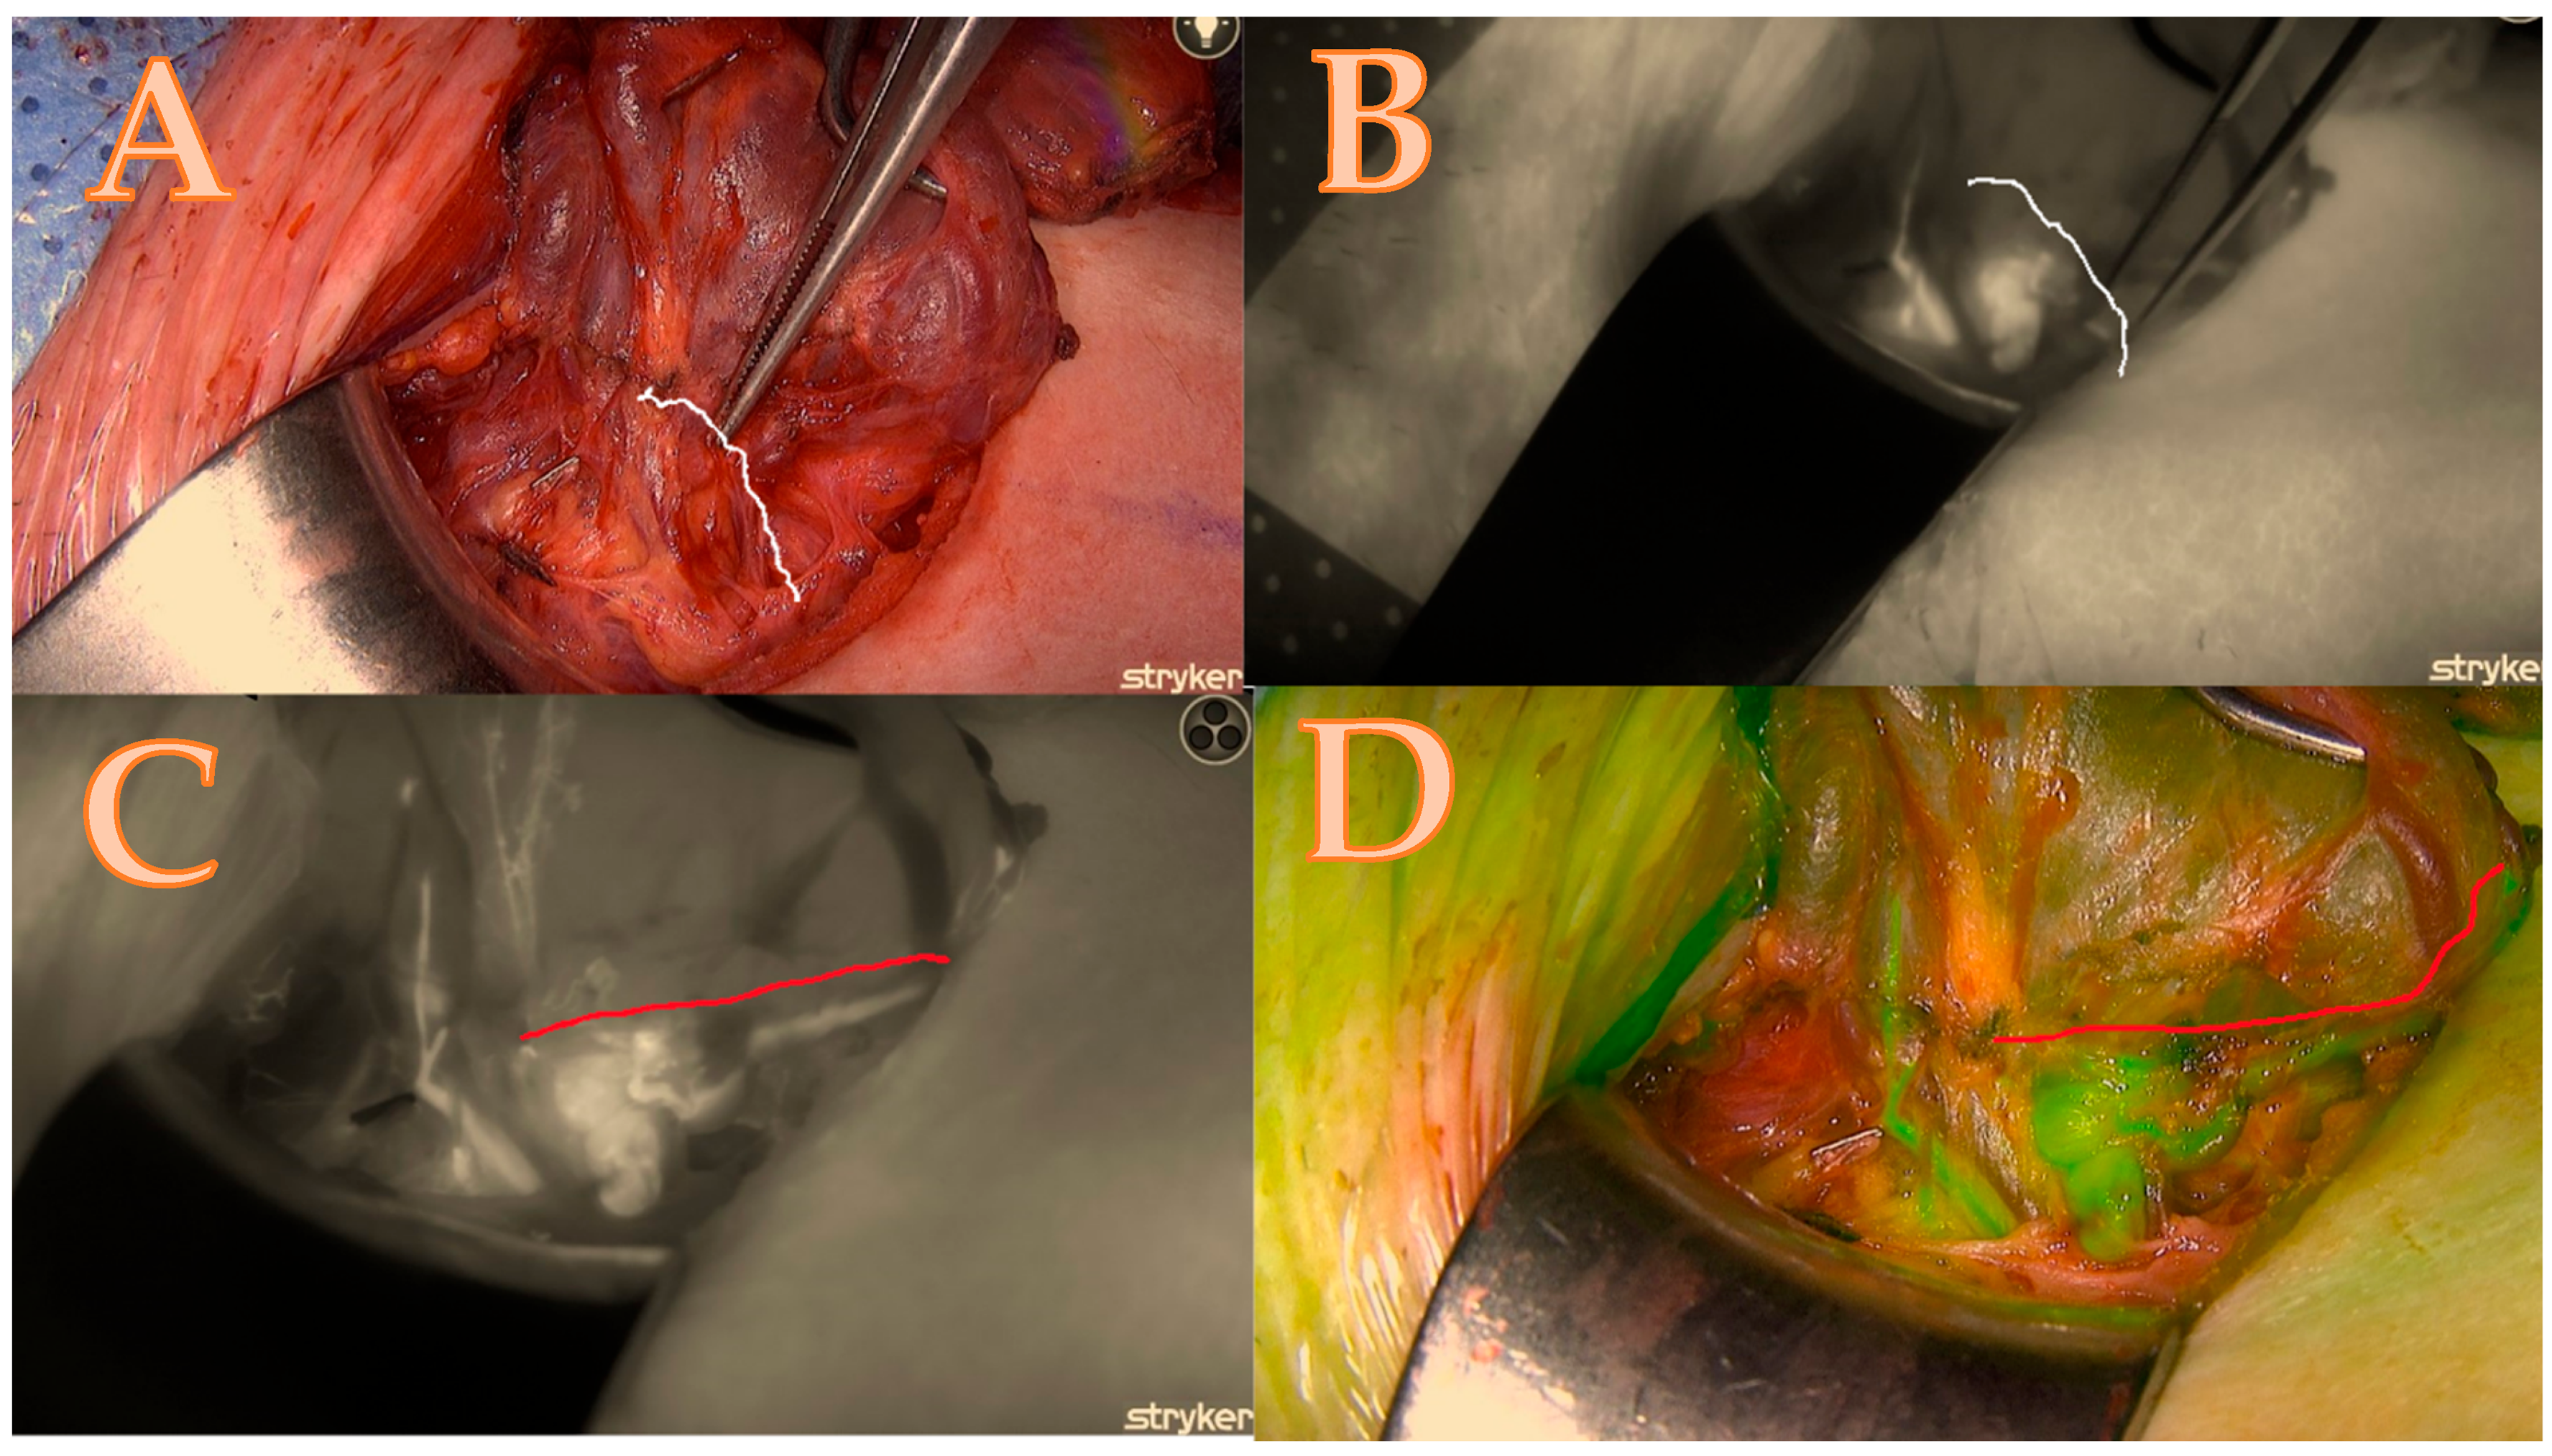

After the thyroid lobe was mobilized in the wound, a 5 mL bolus of ICG-diluted solution (Aurogreen, Aurolab®, Madurai, India) (0.3 mg/kg) was injected intravenously. Simultaneously, the Stryker spy camera was adjusted to the black/white brightness mode and started recording after reducing the theatre light to obtain optimal fluorescence images. Approximately 90 s after the intravenous injection, the Stryker near-infrared fluorescence system began to detect the fluorescence signal given by the ICG. This allowed for the real-time identification of the blood arteries that feed the parathyroids, which are of primary importance and can change the strategy of dissection as seen in Figure 1A–D.

Figure 1.

Right lower parathyroid; (A) is a native picture that represents the initial step of the Burjeel ICG technique, while the white line represents the theoretical dissection pathway using a classical technique without ICG. (B) The initial ICG brightness and vascular path of the black-and-white ICG illustration determine the parathyroid dissection pathway without an optimal and final ICG image. (C) = maximum brightness of the ICG illustration in black and white with additional information about the entire circle of blood supply origin that modified the parathyroid dissection pathway shown in the red line; (D) = image confirmation in green mode to minimize errors and contamination with the background.